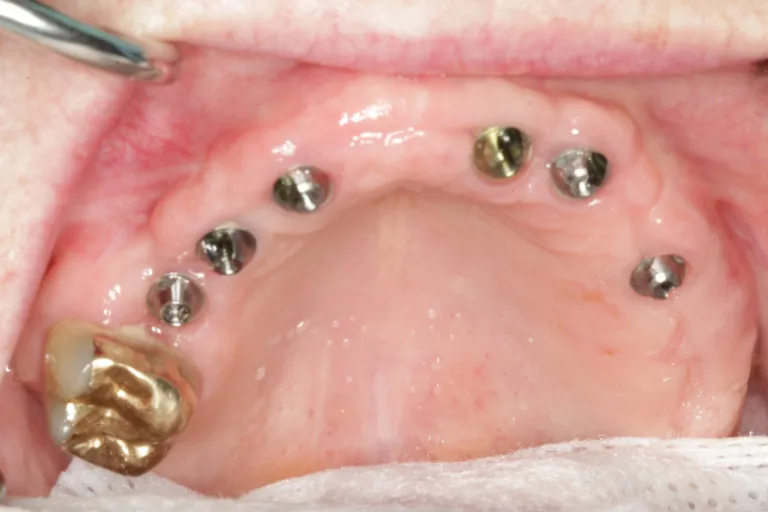

Multiple Dental Implants IMPrESS Perio Implant Center Burnaby Implant Specialist Vancouver Implant Center Dr. Mehdi Noroozi Implant Specialist in BC